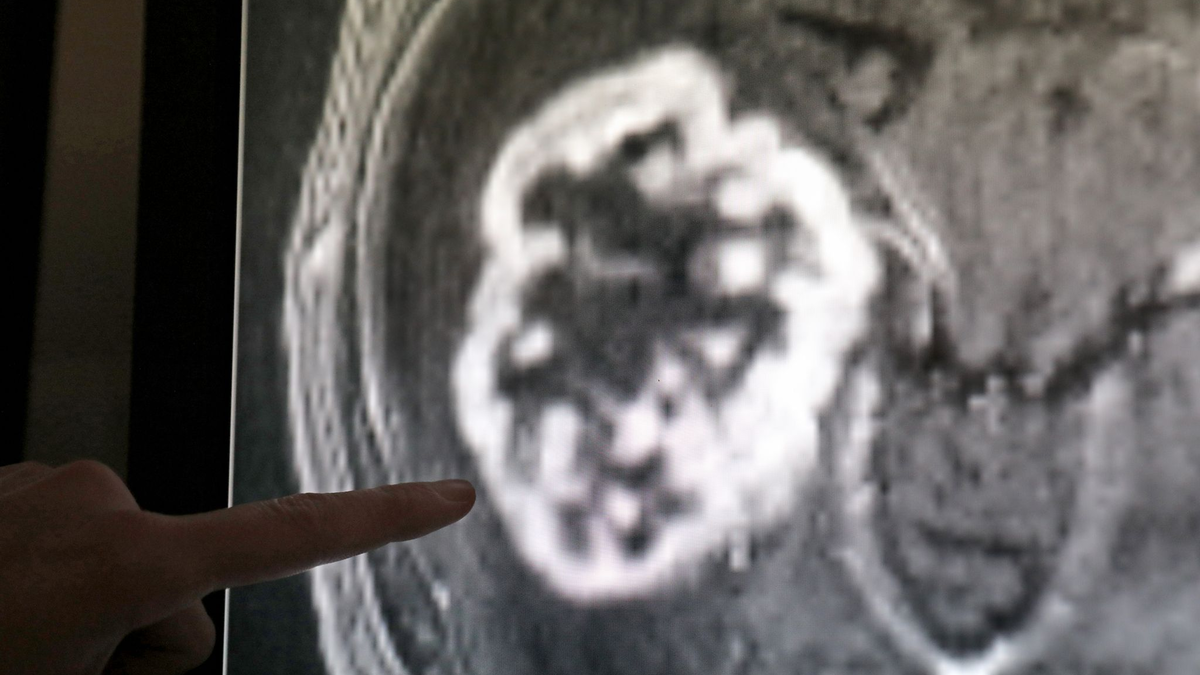

Da die Moleküle sehr charakteristisch für bestimmte Gewebetypen sind, lassen sie sich auch in der Diagnostik einsetzen, wie Diederichs erklärte. Bei Bauchspeicheldrüsen- und Lungenkrebs könnte dies nicht nur helfen, Tumore früh zu erkennen, sondern auch, etwaige Therapiefortschritte zu verfolgen. Therapien mit miRNAs würden derzeit geprüft - nicht nur an Bauchspeicheldrüsen-Tumoren, sondern auch bei Lungenkrebs und Hirntumoren.